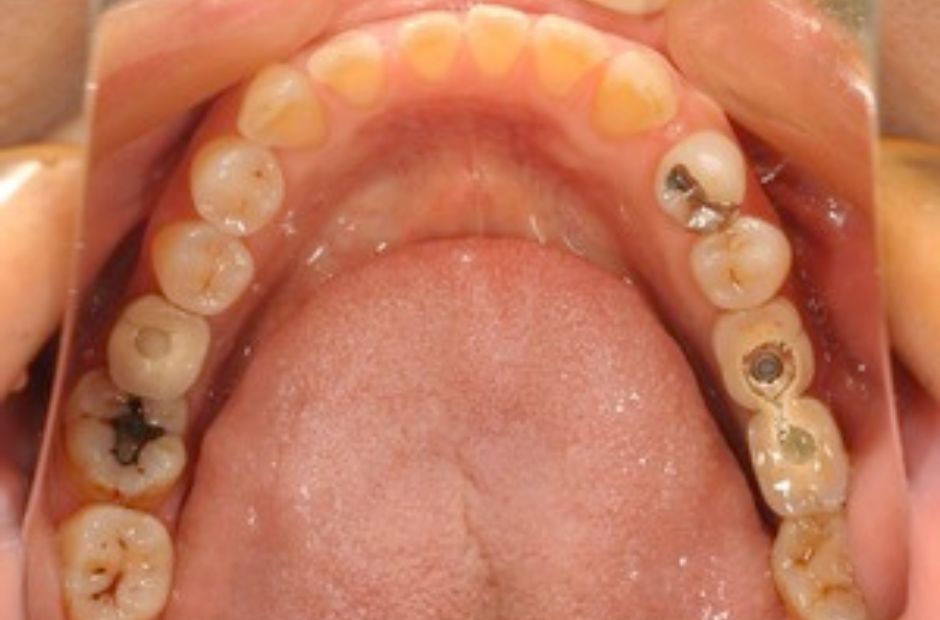

case.03

自然な歯の保存に成功

インプラント治療を希望されていた中高年の患者様が来院されましたが、詳細な検査の結果、虫歯が進行していないことが判明しました。このため、インプラントではなく、根管治療を選択し、自然な歯を保存することに成功しました。この治療は、自然な歯の重要性を重視し、患者様の口腔健康を最優先に考える当院のアプローチを反映しています。治療後、患者様は自然な歯を保つことができ、日常生活の質の向上を実感されました。